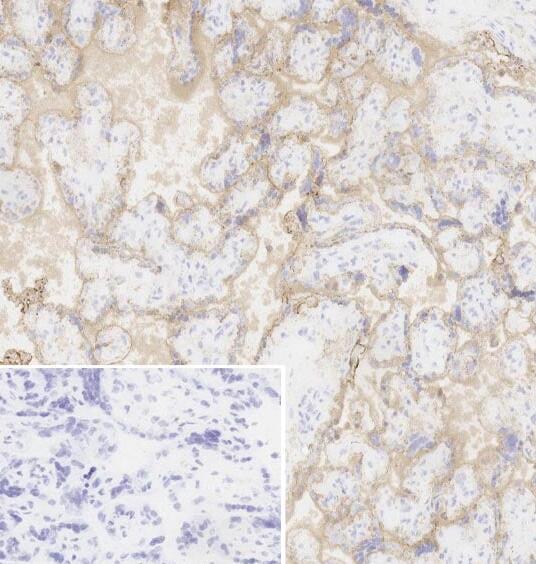

Anti-EGFR抗体[EGFR1]

小鼠单克隆抗体[EGFR1] to EGFR

适用于: IHC-Fr, ICC/IF, Flow Cytmore details

Tissue, cells or virus corresponding to Human EGFR (extracellular). Human epidermoid carcinoma line A431; epitope mapped between aa 6-273 of human EGFR.

• 表位

• IHC-Fr: Frozen normal human placenta ICC/IF: A431 cells Flow Cyt: A 431 cells

Recognises the external EGF-binding domain of the EGFR transmembrane glycoprotein. No effect on tyrosine kinase activity of EGFR.